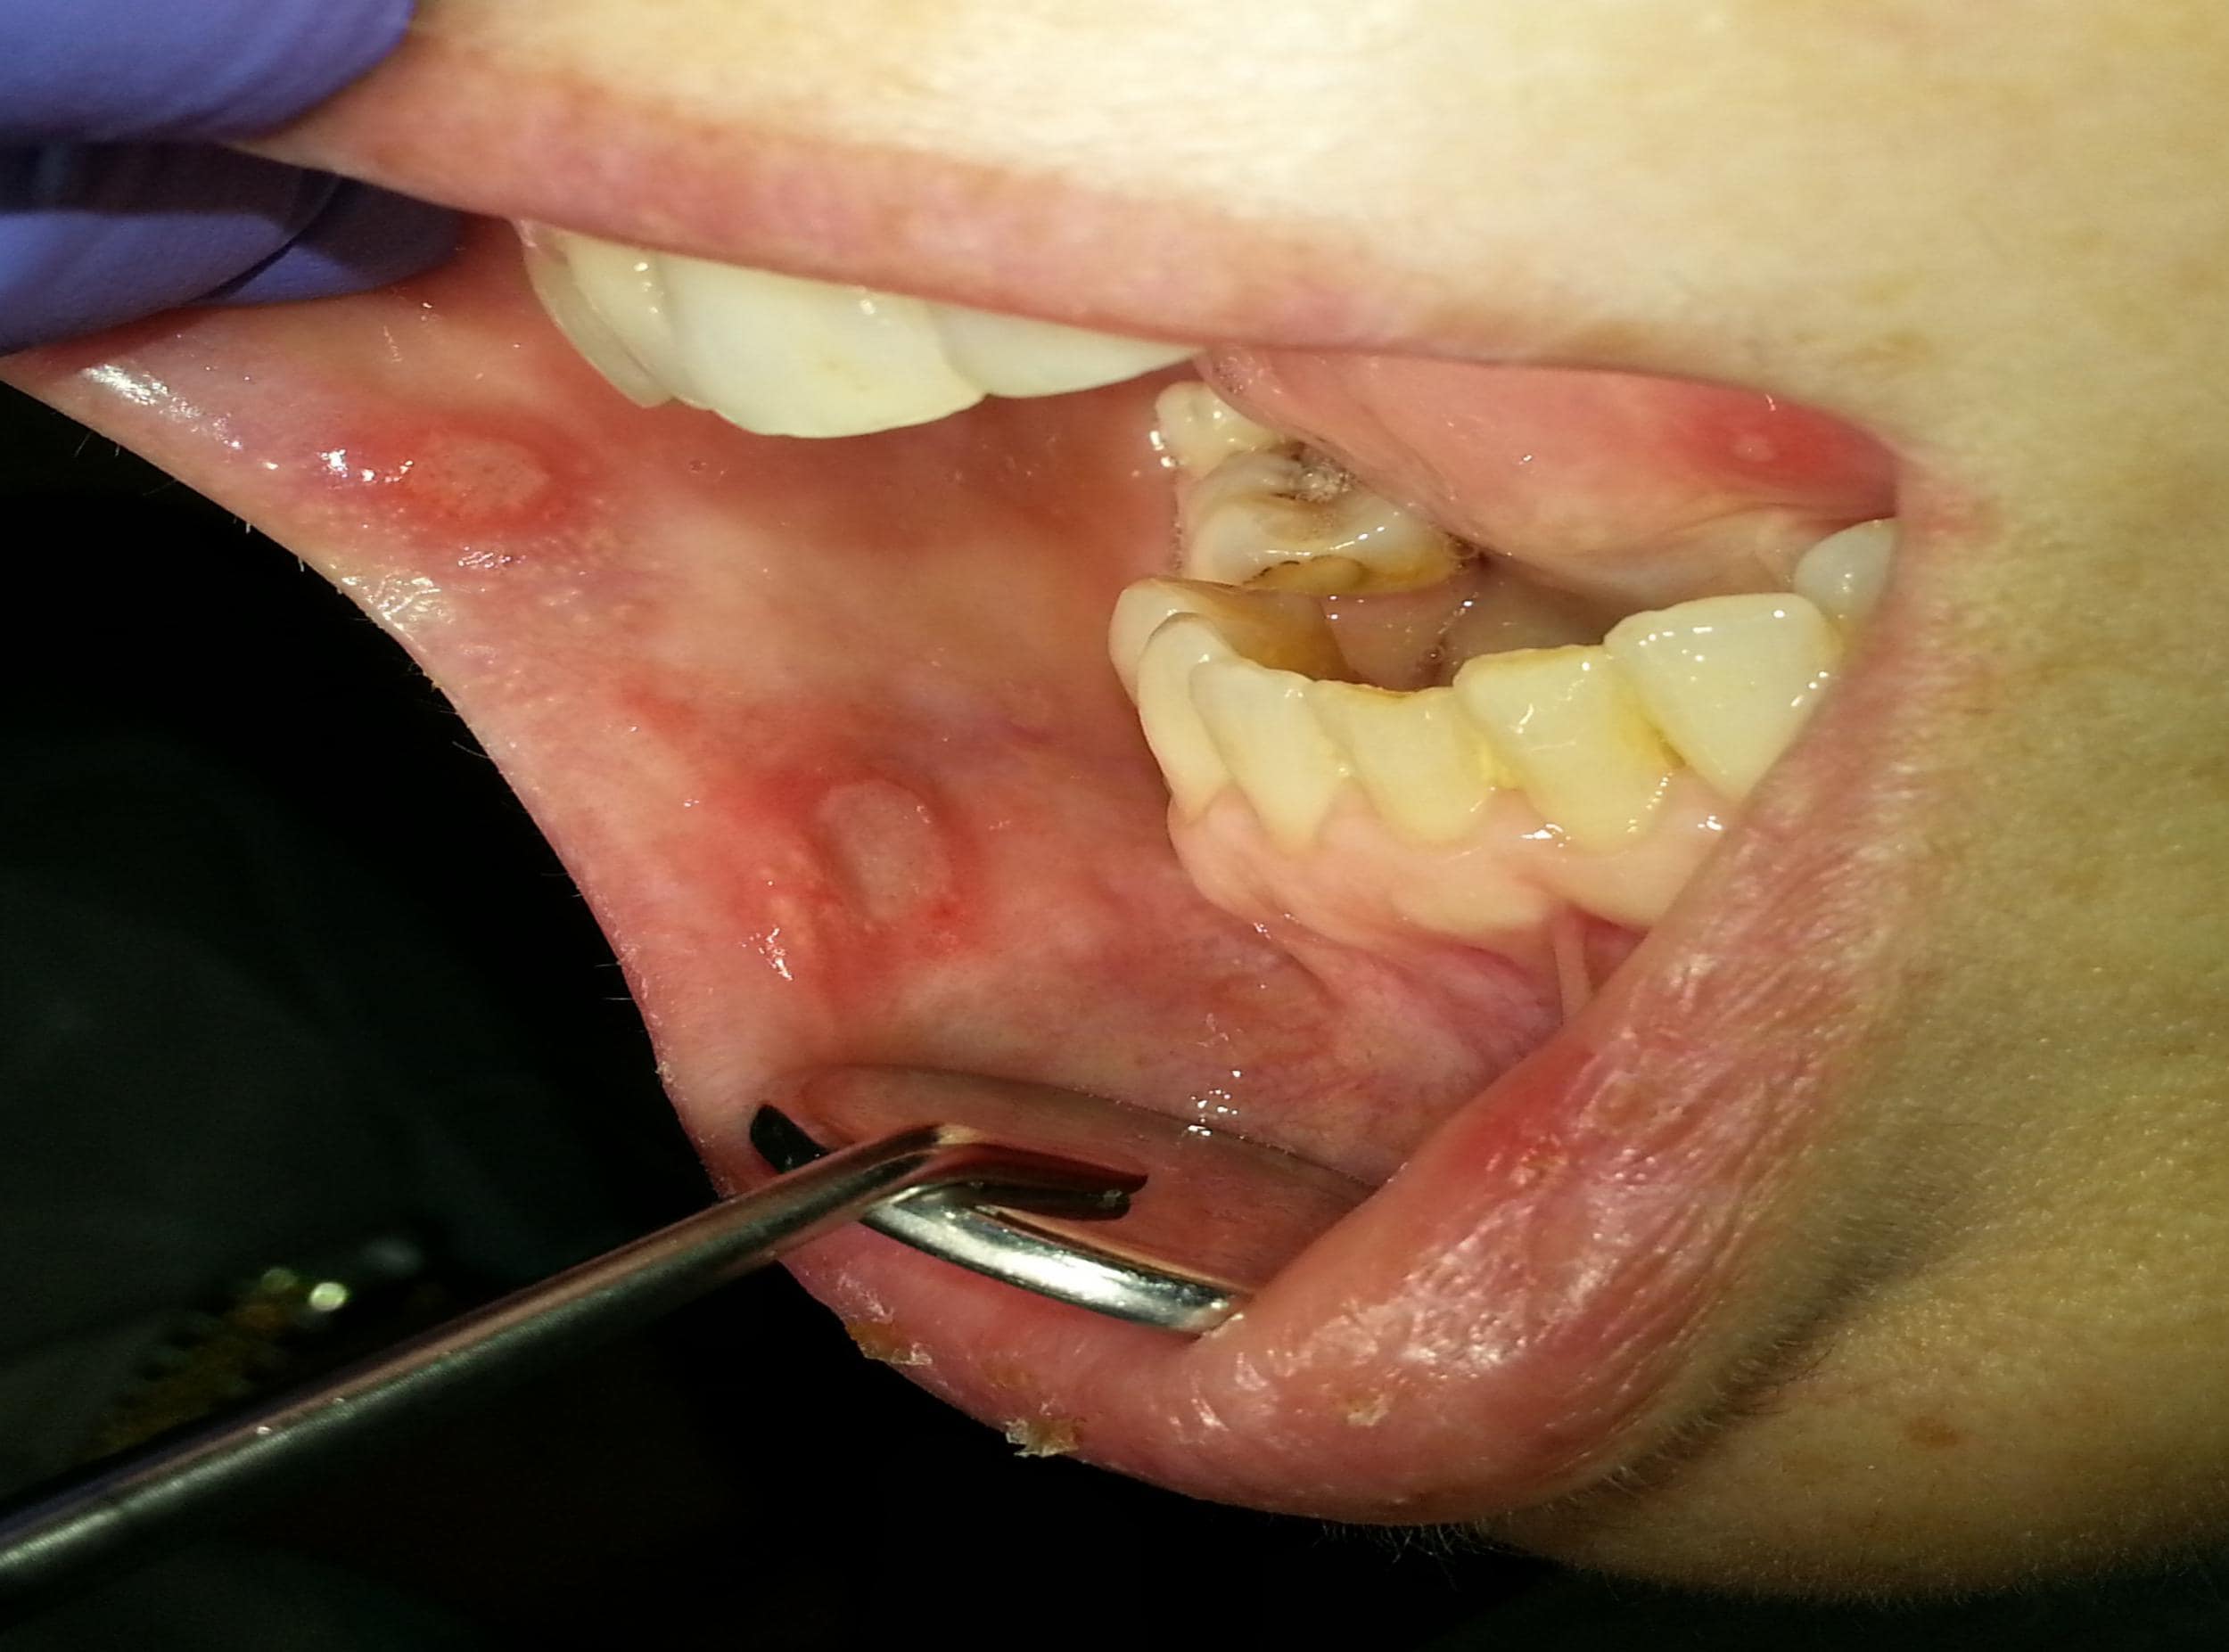

القرحات القلاعية المعروفة أيضا باسم "قروح كانكر" هي أكثر أنواع تقرحات الفم شيوعا وهي عبارة عن آفات التهابية حميدة ومؤلمة تظهر على الأغشية المخاطية الرخوة وغير المتقرنة داخل الفم. على عكس قروح الهربس (المعروفة بقروح الحمى) والتي تظهر عادة على الشفاه من الخارج فإن القرحات القلاعية تتكون في باطن الخدين والشفاه وتحت اللسان أو على الحنك الرخو وهي ليست معدية على الإطلاق. تبدأ القرحة غالبا كإحساس حارق أو وخز يستمر لمدة يومين ثم تتطور إلى قرحة بيضاوية أو مستديرة الشكل ذات قاع أصفر-رمادي ومحاطة بحافة حمراء ملتهبة وواضحة.

القرحات القلاعية الكبيرة (Major Aphthous Ulcers):

هذا النوع أقل شيوعا ولكنه أكثر شدة ويمثل حوالي 10% من الحالات. تكون القرحات أكبر حجما (غالبا أكبر من 1 سم) وأكثر عمقا وألما. تستغرق وقتا أطول للشفاء قد يمتد لأسابيع أو أشهر وغالبا ما تترك ندبة بعد التئامها.

علاقتها بالأمراض الجهازية

في بعض الأحيان لا تكون القرحات القلاعية مجرد حالة فموية معزولة بل قد تكون عرضا مبكرا أو مصاحبا لأمراض جهازية أكثر خطورة. من المهم جدا أخذ هذه الاحتمالات في عين الاعتبار خاصة إذا كانت القرحات شديدة أو متكررة جدا. من هذه الأمراض:

- مرض بهجت (Behçet's Disease): وهو اضطراب التهابي مزمن يؤثر على الأوعية الدموية في جميع أنحاء الجسم وتعد تقرحات الفم المتكررة من أبرز أعراضه إلى جانب تقرحات الأعضاء التناسلية والتهابات العين.

متى تصبح قرحة الفم علامة خطيرة؟

في الغالبية العظمى من الحالات تكون القرحات القلاعية حالة حميدة ومزعجة لكنها غير خطيرة. ومع ذلك هناك بعض العلامات التحذيرية التي تشير إلى أن القرحة قد تكون أكثر من مجرد إزعاج عابر وقد تتطلب تقييما طبيا فوريا. من الضروري الانتباه لهذه الأعراض لاستبعاد الحالات الأكثر خطورة مثل الأمراض الجهازية أو حتى السرطان (في حالات نادرة جدا).

استشر طبيبك أو طبيب أسنانك فورا في الحالات التالية:

- قرحة لا تلتئم: إذا استمرت القرحة لأكثر من ثلاثة أسابيع دون أي علامة على الشفاء. القرحات العادية تشفى عادة خلال أسبوع إلى أسبوعين .

- الحجم الكبير جدا: القرحات الكبيرة بشكل غير معتاد (Major aphthae) تتطلب دائما تقييما.

- تكرار شديد: إذا كانت القرحات تظهر بشكل مستمر بحيث تبدأ قرحة جديدة بالظهور قبل أن تلتئم القرحة القديمة (complex aphthosis).